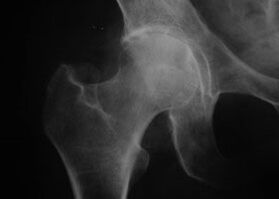

Appearance of a joint with osteoarthritis

Coxatrosis, osteoarthritis of the hip joint.

With this disease, a classic clinical picture of osteoarthritis is observed.

The first symptom of coxarthrosis is discomfort in the hip joint after physical activity.

With progressive coxarthrosis, pain increases, stiffness and limited mobility appear.

Patients with a severe form of coxarthrosis respect the affected limb, avoid stepping on it and, while standing, choose positions in which less pain is felt.